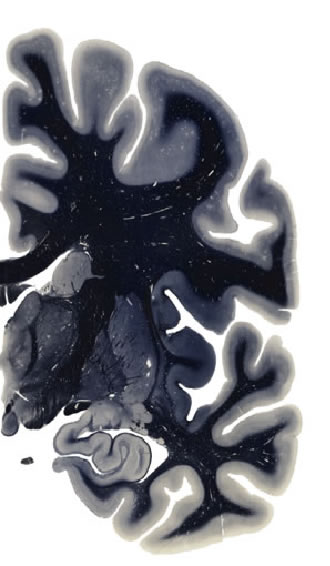

Hi-Resolution Sections · Cells (Nissl Staining) · Virtual Microscopy

Frontal sections (Nissl) from the Atlas Brain:

Slice ID:

r3-0955

Plate NR:

ca 31

Position:

11,9 mm